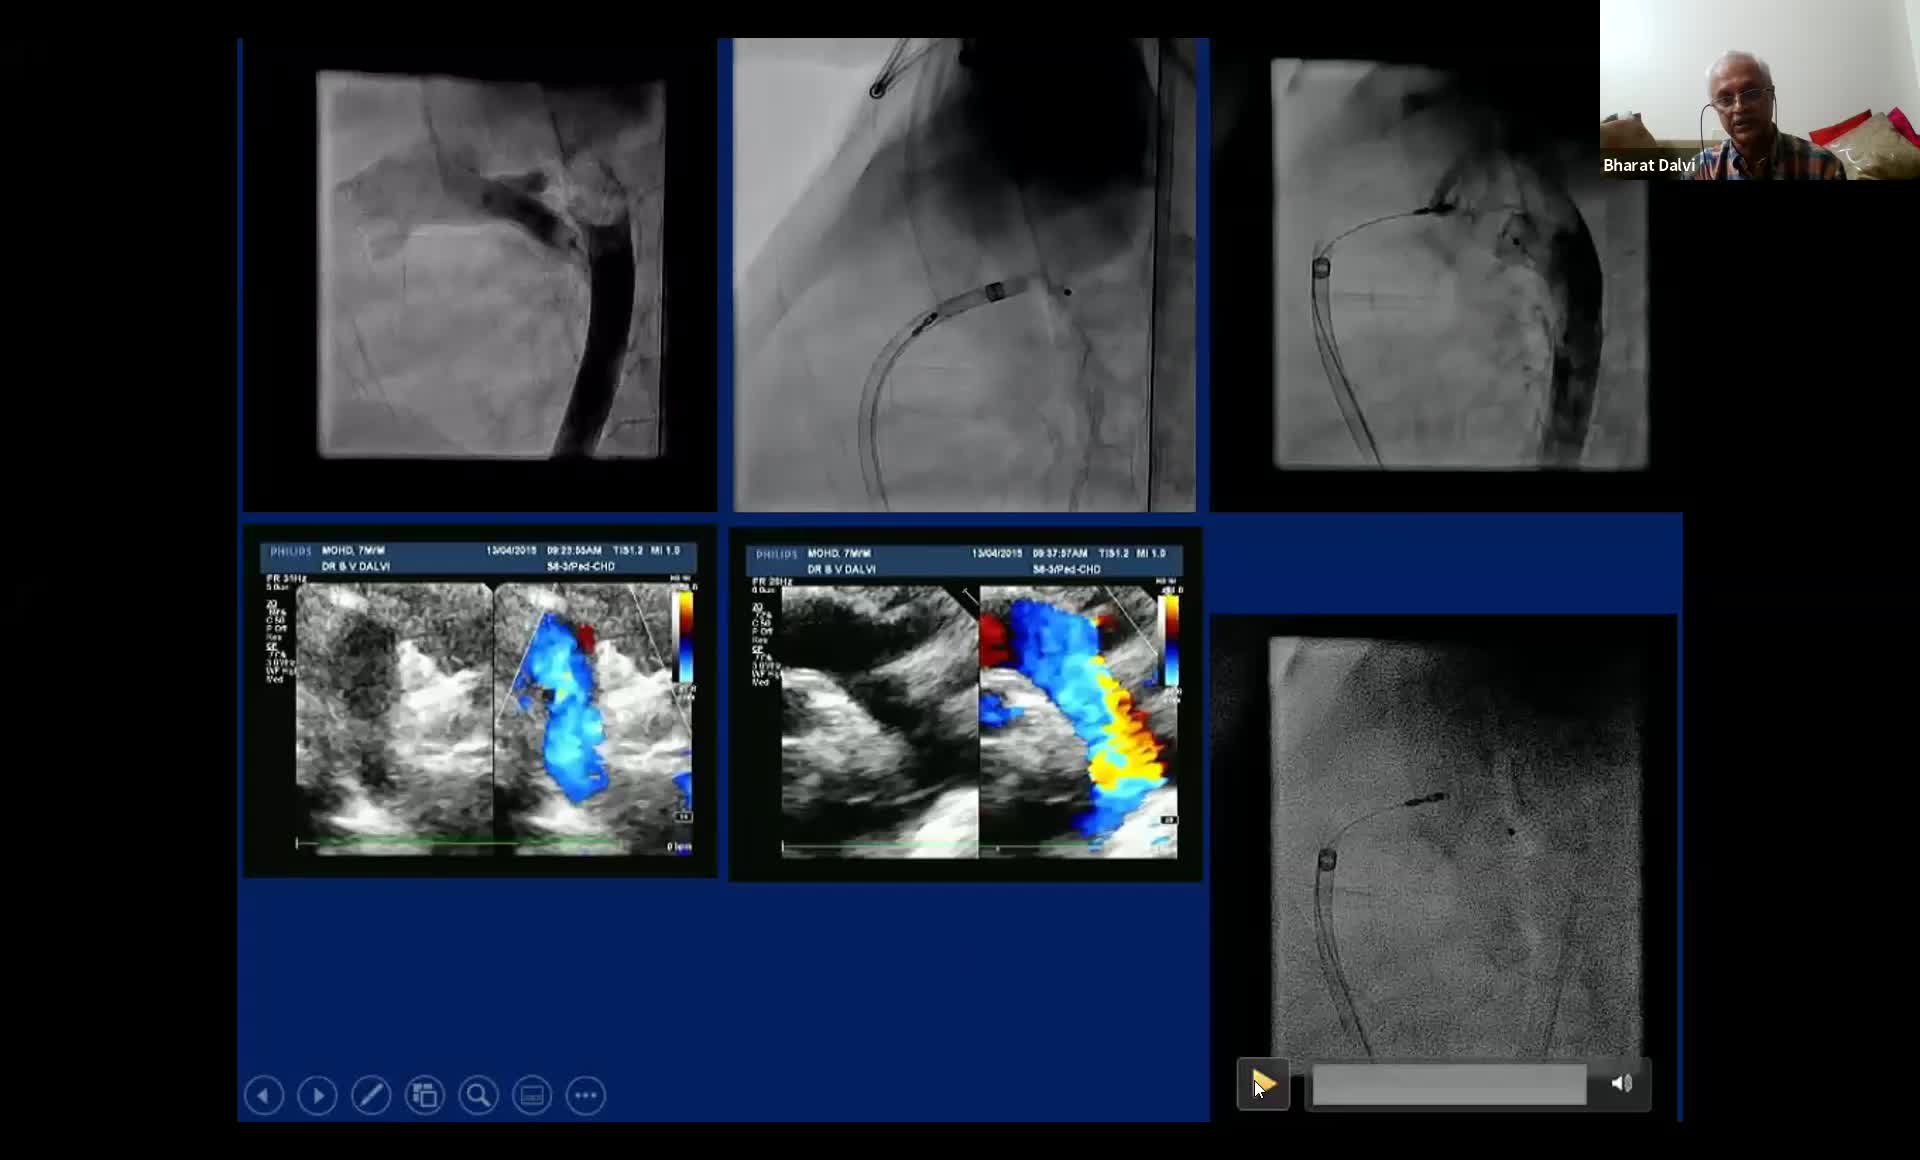

CSI CATHLAB LIVE - VSD CLOSURE WITH THE NEW OCCLUTECH PMVSD OCCLUDER (ANTEGRADE APPROACH)